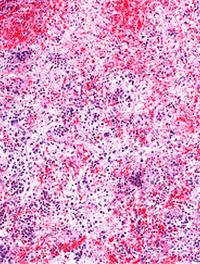

La myélofibrose est un syndrome myéloprolifératif chronique caractérisé par une prolifération clonale, une érythropoïèse inefficace, [...]